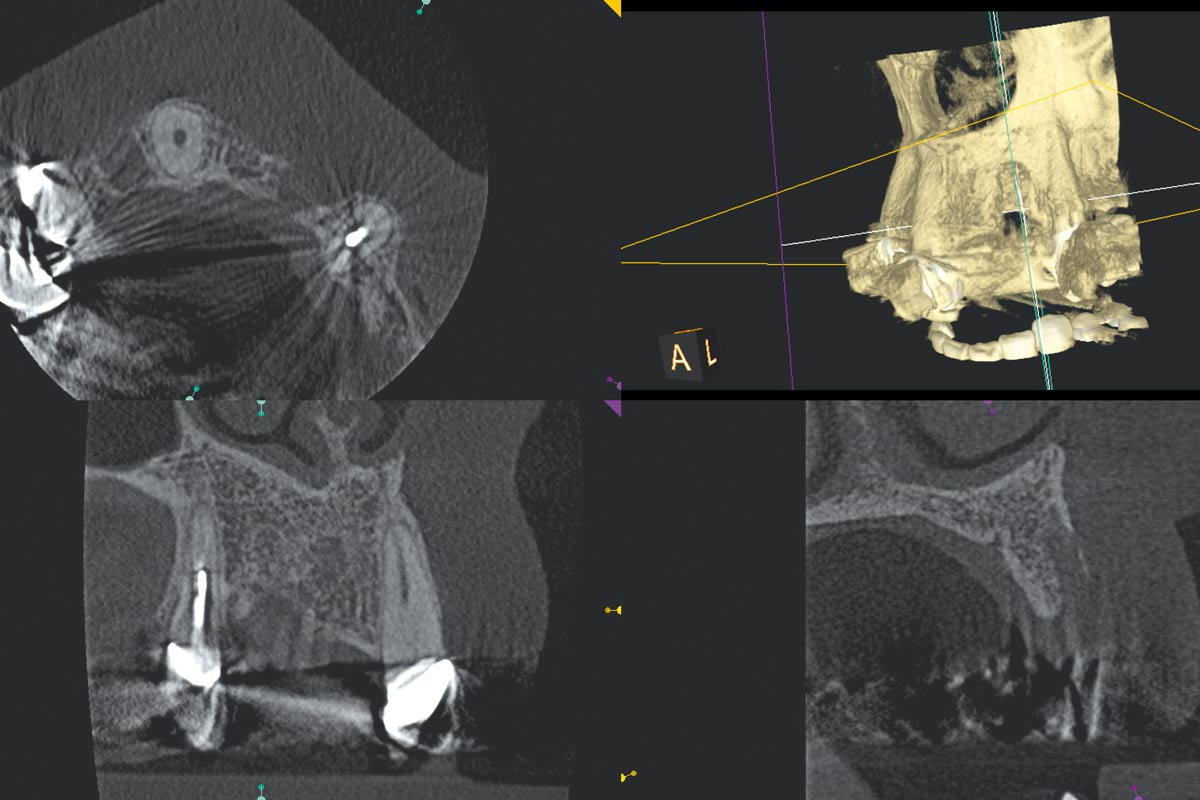

Regeneration of a 9 mm vertical bone defect with cerabone®, autologous bone and S-PRF –  Dr. A. Eslava

Initial x-ray showing bone loss around implants placed 5 years ago in another dental clinic